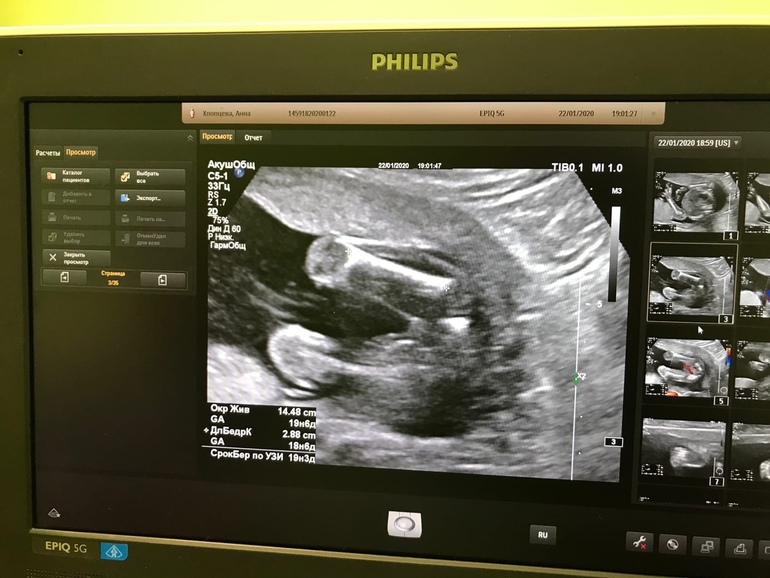

Вот в 19 недель